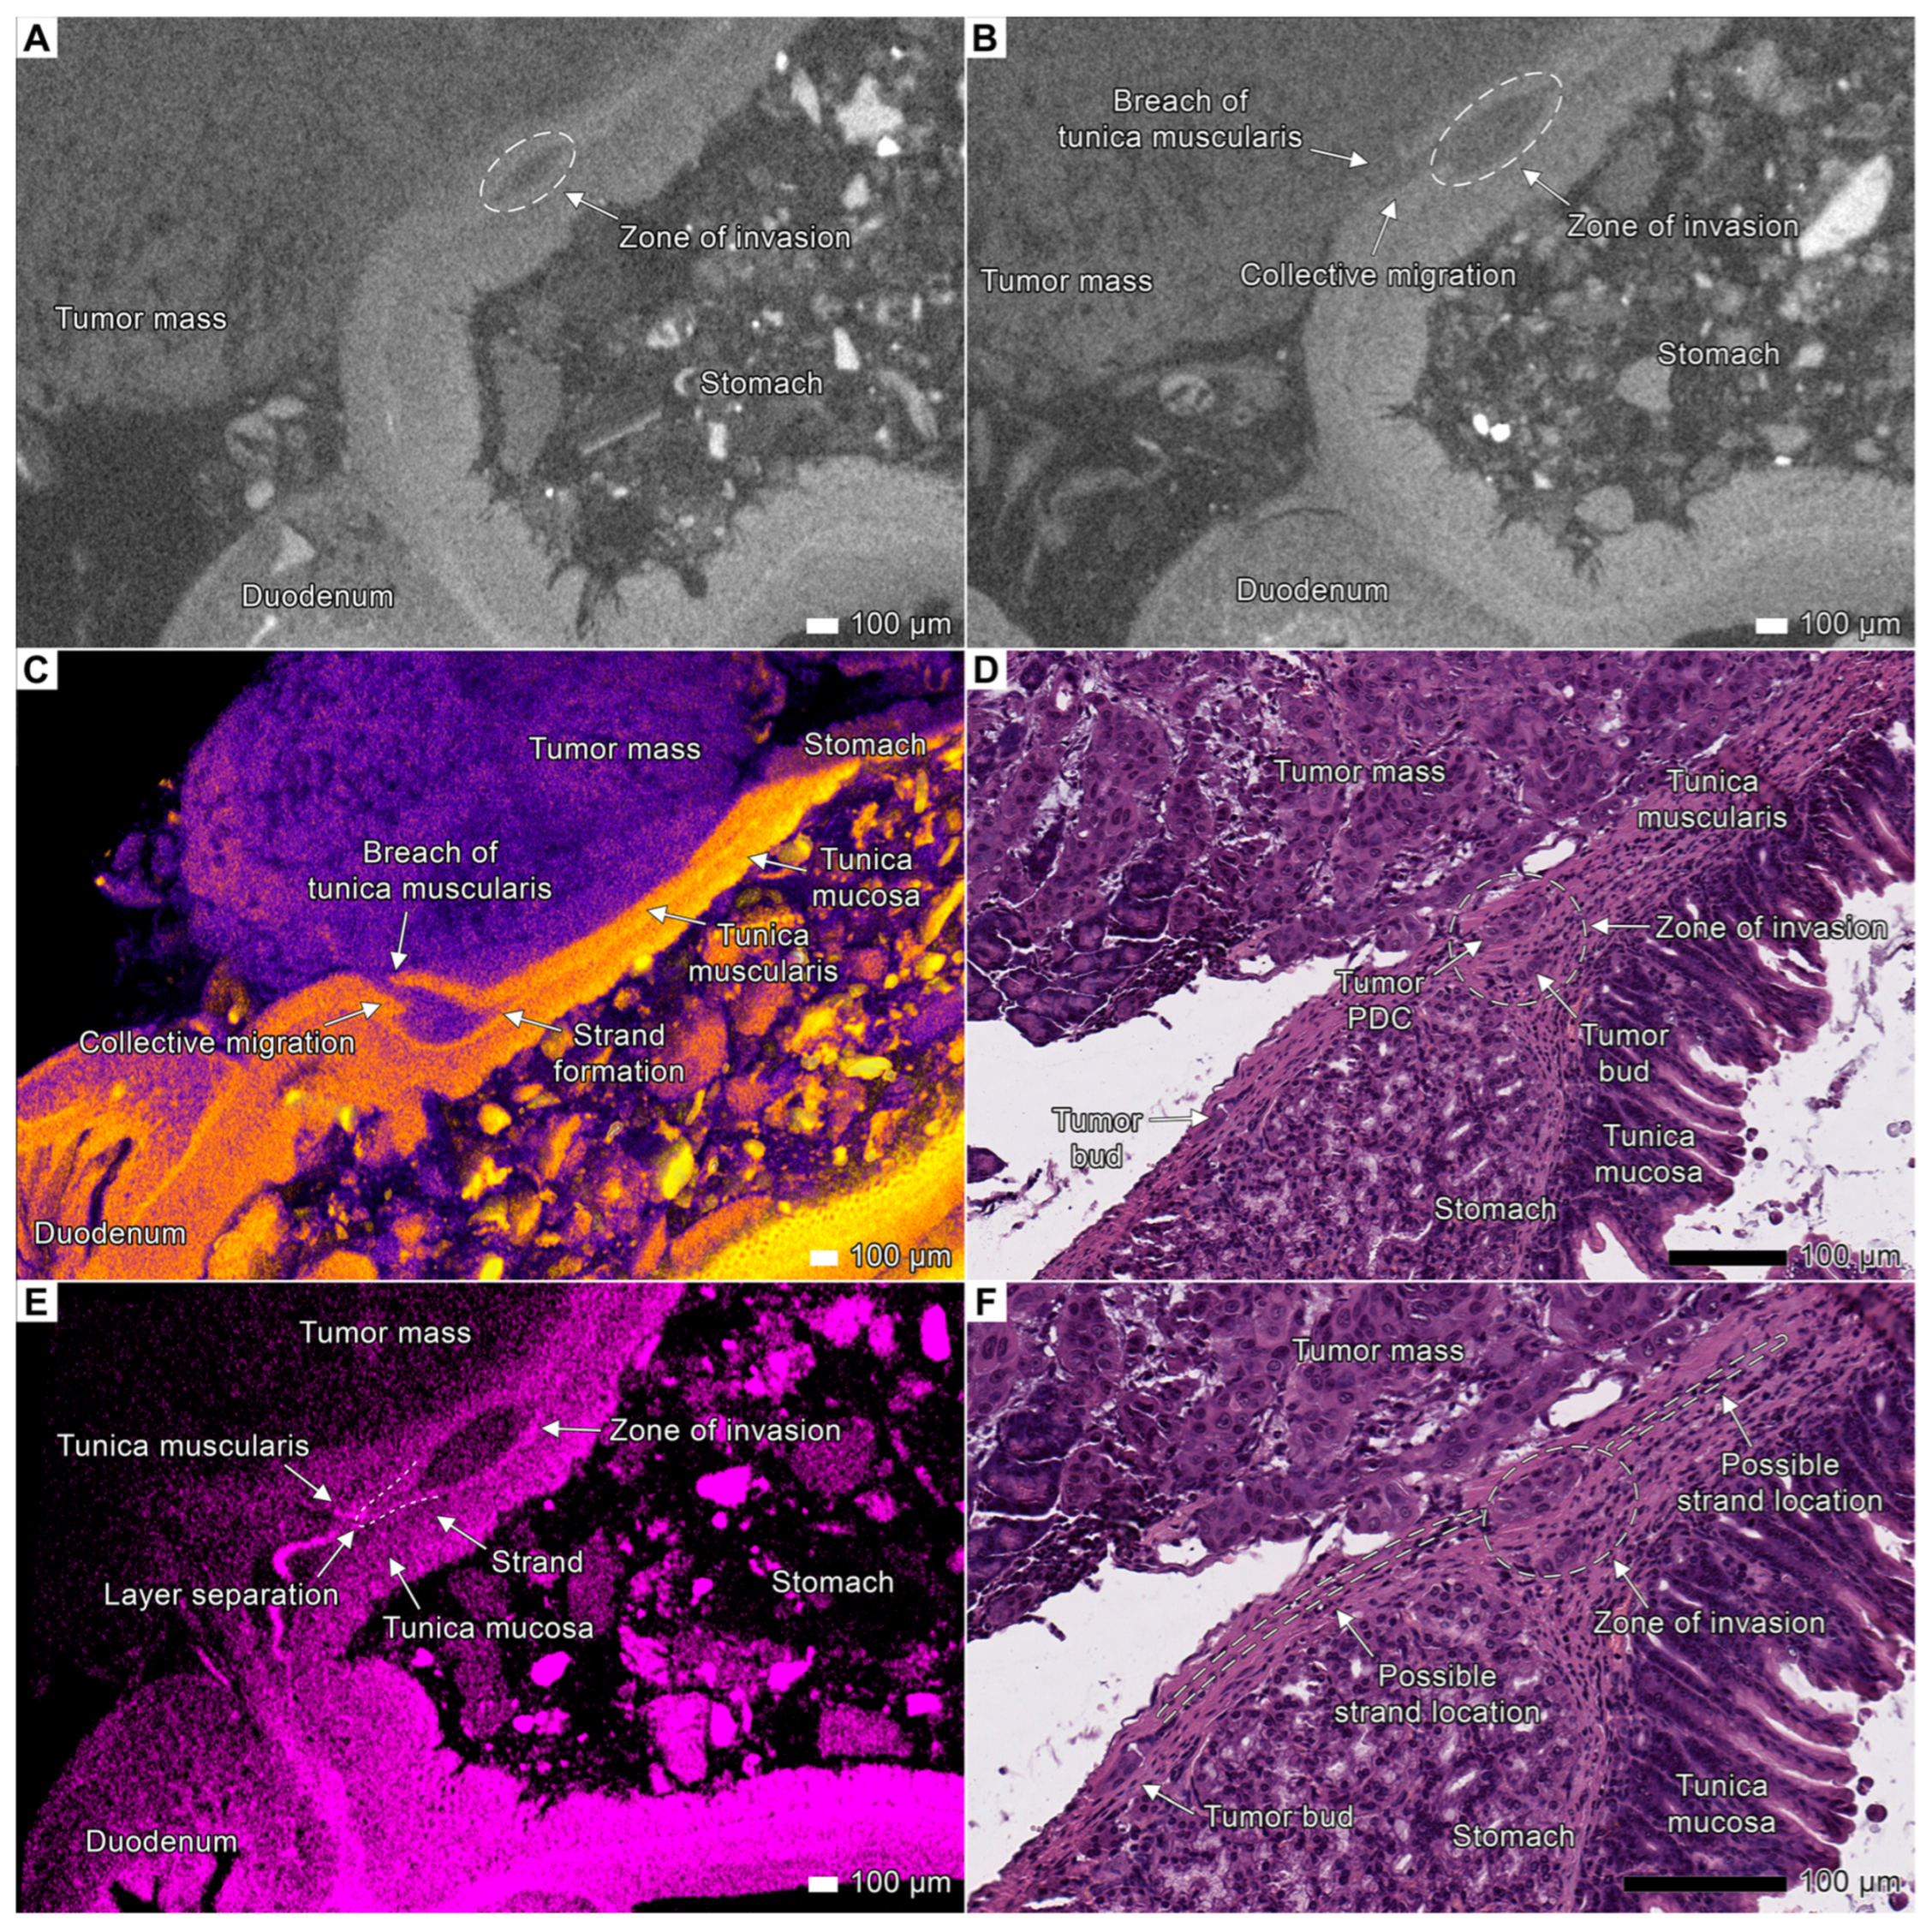

3.2. Tumor Invasion into the Esophagus and Stomach

4.1. Visualization of Tumor Invasion

4.3. Invasion Patterns

4.4. Tumor Budding Revisited

4.5. Tumor Invasion as a Process of Coordinated Tissue Remodeling